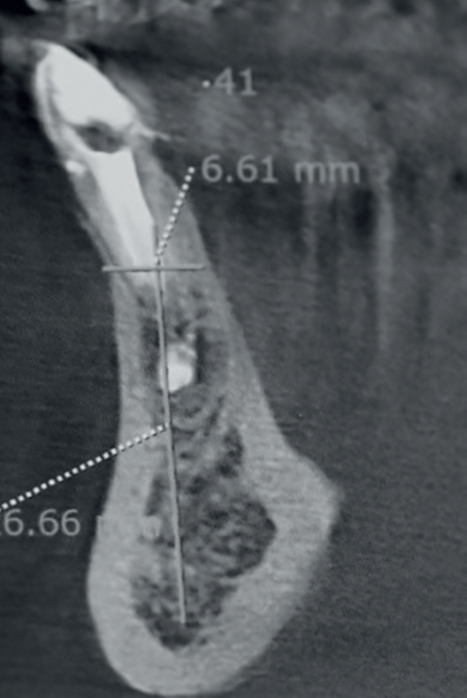

Um paciente com 49 anos de idade buscou atendimentoem clínica privada devido à fratura após um retratamento endodôntico no dente 41 (Figura 1). Mediante a anamnese e análise do exame de tomografia computadorizada de feixe cônico solicitado, foi verificada qualidade óssea do tipo II na área. Então, a decisão clínica baseou-se na cirurgia para exodontia e instalação imediata de um implante dentário.

Após a assepsia com clorexidina 2% e anestesia terminal infiltrativa com mepivacaína 2% com epinefrina 1:100.000, foi selecionado um implante dentário cônico Due Cone (3,5 mm x 13 mm). Foi utilizada a sequência de fresagem com fresa lança helicoidal 2 mm e fresa de 3,5 mm, conforme recomendações do fabricante. O implante foi estabilizado com torque de 45 Ncm. A sutura foi realizada com fio de sutura de seda 4-0, e uma prótese provisória adesiva foi instalada apoiada sobre os dentes vizinhos (sem preparo dentário), permanecendo durante as 12 semanas de espera para o segundo tempo cirúrgico (Figuras 2 e 3).